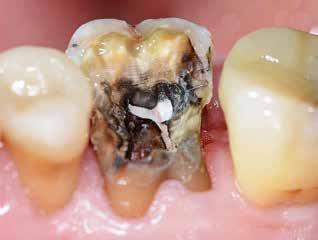

Knækket rodfil

i distal kanal -6

PATIENTTILFÆLDE

Patienten henvender sig på klinikken pga. akutte smerter fra -6. Der laves akut oplukning og findes tre kanaler. Ved udrensning i distale kanal for at finde endeligt rodmål knækker ca. 1-2 mm af fil 08 i kanalen. Patienten bliver informeret og henvist til specialtandlæge for videre behandling.

LÆRING

Det fremgår, at der er tale om en filstørrelse 08, altså den tyndeste fil, der findes. Ved flerrodede tænder med lange, krumme og/eller oblitererede (“tilgroede”) rodkanaler er risikoen for filfraktur højere.

Det anbefales derfor, at du anvender meget fleksible file, skyller kanalerne hyppigt undervejs og kasserer file, der udviser svaghedstegn (fx vrid eller buk på filens arbejdende del). Du bør desuden kassere de mindste file efter brug, da risiko for usynlige svagheder i disse er høj. Alternativt kan du henvise til en tandlæge med særlig kompetence inden for rodbehandling, hvis du vurderer, at en rodbehandling er særligt vanskelig.

Se også guiden "Sådan fjerner du et filfragment" på side 774.